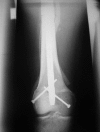

Although functionally appealing in preserving the native knee, the condyle-sparing intercalary allograft of the distal femur may be associated with a higher risk of tumor recurrence and endoprosthetic replacement for malignant distal femoral bone tumors. We therefore compared the risk of local tumor recurrence between patients in these two types of reconstruction groups. We retrospectively reviewed 85 patients (mean age, 22 years; range, 4-82 years), 38 (45%) of whom had a condyle-sparing allograft and 47 (55%) of whom had endoprostheses. The minimum followup for both groups was 2 years (mean, 7 years; range, 2-19 years). Local recurrences occurred in 11% (five of 47) of the patients having implants versus 18% (seven of 38) of the patients having allografts. Using time to local recurrence as an end point, the Kaplan-Meier survivorship of the implant group was similar to that of the condyle-sparing allograft group at 2, 5, and 10 years (93% versus 87% at 2 years, 87% versus 81% at 5 years, and 87% versus 81% at 10 years, respectively). The condyle-sparing allograft procedure offers the potential advantage of retaining the native knee in a young patient population while incurring no greater risk of local recurrence as those offered the endoprosthetic procedure.